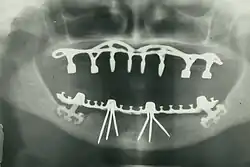

В настоящее время стоматология шагнула далеко вперёд. Стала возможной имплантация зубов и восстановление даже очень сильно разрушенного зуба, появились качественные пломбировочные материалы и современные инструменты для лечения зубов. При этом имплантация зубов возможна как при единичной потере зуба, так и при полном их отсутствии, для этого используют технологию вживления искусственного корня в костную ткань челюсти — зубных имплантатов, что даёт возможность восстановить сегменты зубного ряда зубными имплантатами без нарушения целостности и функциональности рядом стоящих здоровых зубов.